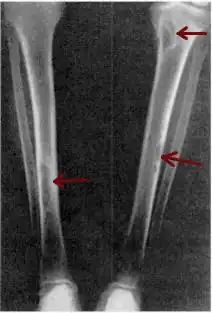

| Osteitis fibrosa cystica of the tibia. Arrows point to the brown tumors which are typically present in bones of people with OFC. | |

Osteitis fibrosa cystica (/ˌɒstiˈaɪtɪs faɪˈbroʊsə ˈsɪstɪkə/ OSS-tee-EYE-tis fy-BROH-sə SIS-tik-ə) is a skeletal disorder resulting in a loss of bone mass, a weakening of the bones as their calcified supporting structures are replaced with fibrous tissue (peritrabecular fibrosis), and the formation of cyst-like brown tumors in and around the bone. Osteitis fibrosis cystica (OFC), also known as osteitis fibrosa, osteodystrophia fibrosa, and von Recklinghausen's disease of bone (not to be confused with von Recklinghausen's disease, neurofibromatosis type I), is caused by hyperparathyroidism, which is a surplus of parathyroid hormone from over-active parathyroid glands. This surplus stimulates the activity of osteoclasts, cells that break down bone, in a process known as osteoclastic bone resorption. The hyperparathyroidism can be triggered by a parathyroid adenoma, hereditary factors, parathyroid carcinoma, or renal osteodystrophy. Osteoclastic bone resorption releases minerals, including calcium, from the bone into the bloodstream, causing both elevated blood calcium levels, and the structural changes which weaken the bone. The symptoms of the disease are the consequences of both the general softening of the bones and the excess calcium in the blood, and include bone fractures, kidney stones, nausea, moth-eaten appearance in the bones, appetite loss, and weight loss.

Cysts may be lined by osteoclasts and sometimes blood pigments, which lend to the notion of "brown tumors." Such cysts can be identified with nuclear imaging combined with specific tracers, such as sestamibi.[3] Identification of muscular degeneration or lack of reflex can occur through clinical testing of deep tendon reflexes, or via photomotogram (an achilles tendon reflex test).[24][32]